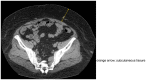

Case presentation: A 24-year-old male patient with Prader-Willi syndrome presented with an enlarged adrenal tumor. Computed tomography detected a well-defined mass. Magnetic resonance imaging revealed an increased signal intensity predominantly in fatty areas, suggesting adrenal myelolipoma. Laparoscopic left adrenalectomy was performed. Postoperatively, the patient developed mild pulmonary atelectasis, myelolipoma was confirmed by histopathology, and there was no recurrence at approximately 2 years postoperatively.